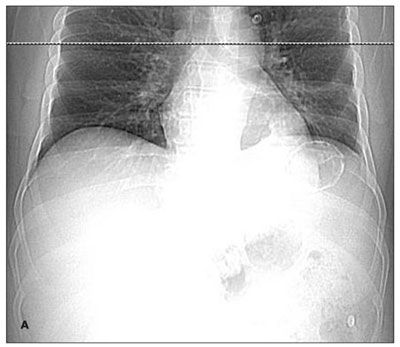

A 38-year-old man found lying on the floor in his home was hospitalized because of alcohol intoxication. A chest radiograph showed a large calcified lesion in the left upper abdomen (A). A CT scan with intravenous contrast revealed a large, well-defined, cystic mass with mural calcification in the spleen (B). The CT findings were not consistent with a vascular malformation or echinococcal cyst-specifically, the mass was sharply demarcated, unilocular without septations, and round with a thin wall and attenuation similar to water. Urine Histoplasma antigen test results were negative.